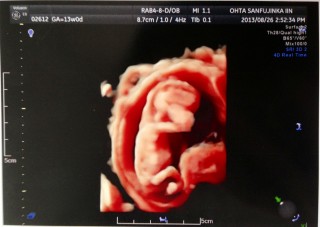

初めての妊娠♪(/ω\*)お腹の上から4Dエコーしてもらうとクネクネ動く姿が…♡残念ながら、後ろすがたしか見えなかったけど、腕や耳までちゃんとあるのが見れて感激♪

エコーをあてると、激しく動いていて、中々綺麗に撮れなくて、 先生が苦労されてやっと撮れた奇跡の1枚です。 ニッコリ笑っていて、嬉しさ倍増です。 身長約8.1センチ。

妊娠してる事に気づかず生理不順かな?って思って病院に行ったら初妊娠で13週目と言われビックリしました(>_<) 先生に凄く元気がいいですね^ ^って言ってもらったりエコー動画見たらなんだか嬉しくなりました^ ^ もっと早くに気づいたらよかった( ; ; ) 彼氏も大喜びでこれから大っきくなっていくのが楽しみです☆

CRL7.08㎝でした。